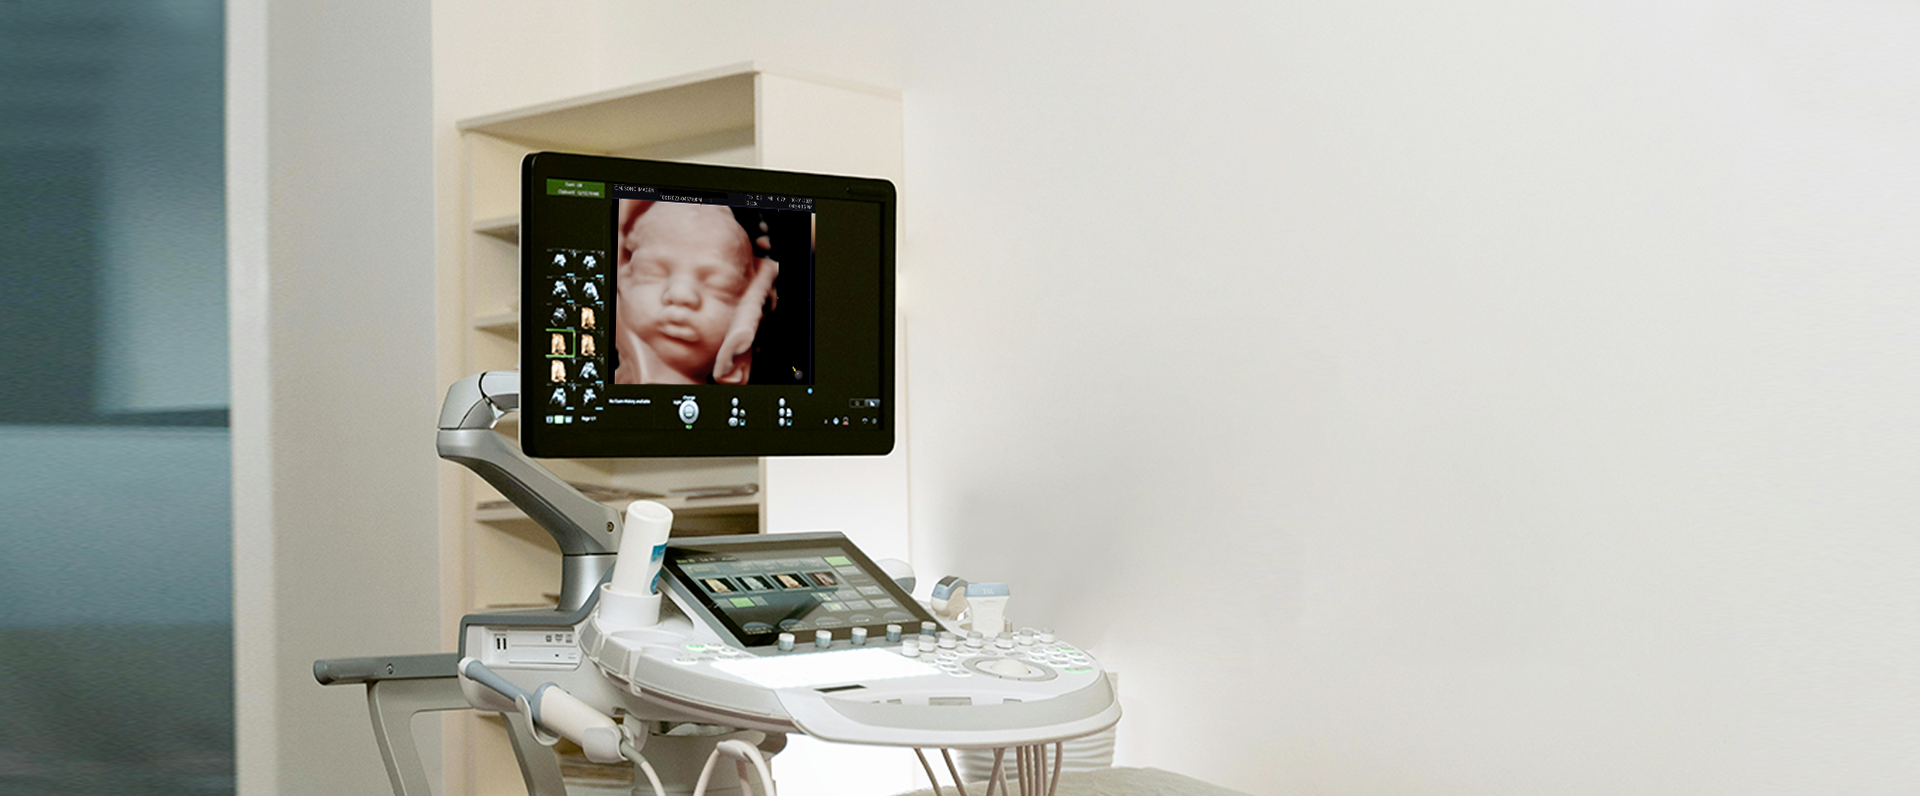

Ecógrafos de vanguardia

Apostamos por la tecnología de vanguardia. Que permite diagnósticos más certeros, y también proporciona una experiencia más cómoda y eficiente para nuestros pacientes. Combinamos la innovación tecnológica con la experiencia de nuestro equipo médico para asegurar resultados rápidos, confiables y orientados a la mejora continua.